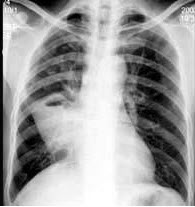

81、单项选择题

男,54岁,咳嗽咳痰,胸痛,痰中带血丝,近2月明显,消廋乏力,有吸烟史30余年,胸片如图,最可能的诊断是()

A.左肺结核瘤

B.肺转移瘤

C.炎性假瘤

D.原发性肺癌

E.结节病